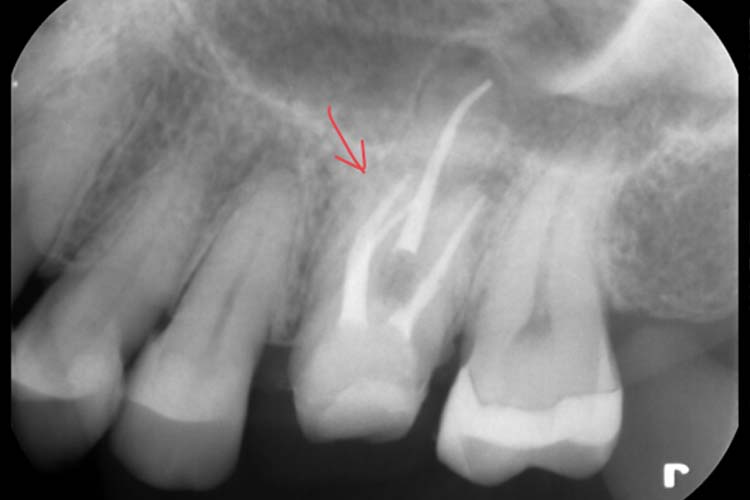

初診時デンタル所見

根尖病変(+) ←根の先を覆う黒い影(透過像)

3根管ともに根管充填がやや疎

MB2の見逃し、緊密に根管充填がなされていないことが再感染の原因と考えられます。